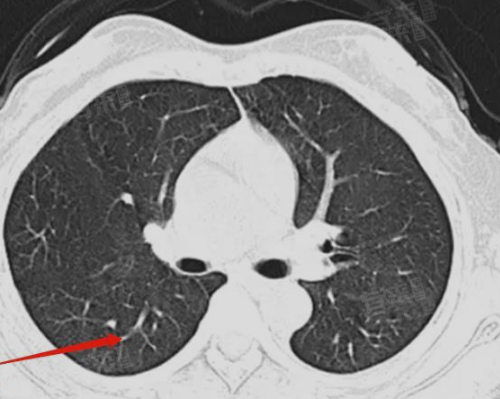

右肺叶少许条索影是肺部影像学检查结果的一种描述,通常指的是在肺部CT或X光检查中,发现右肺叶存在少量的条索状或线状的高密度阴影。这种阴影可能由多种原因引起,如陈旧性病变、肺炎、支气管炎等,形态和分布特点有助于医生判断病因。

1、陈旧性病变:既往患有肺炎、肺结核等肺部疾病,在疾病痊愈后,肺部可能留下瘢痕组织,此类瘢痕在影像学上表现为条索影。这种情况下,患者通常没有呼吸道症状,且条索影不会对身体产生明显影响,一般不需要特殊治疗,只需定期复查即可。